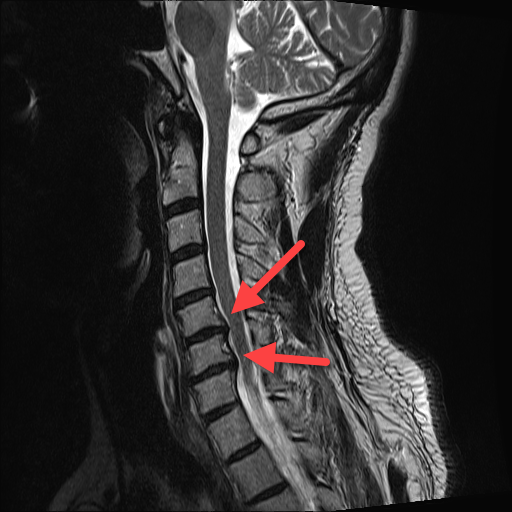

Aus der beliebten Serie "Das kleine Krankenhaus am Rande der Stadt" hier mal ein Update zu meiner Krankenakte. Ich hab ja schon länger Probleme mit der Halswirbelsäule und vor ein paar Jahren wurden schon zwei (eher zweieinhalb) Bandscheibenvorfälle diagnostiziert. Nun war ich letzten Monat nochmal beim MRT, um zu gucken, ob sich das verschlimmert hat. Hat es leider. Hatte heute nochmal einen Termin beim Neurochirurgen. Blöderweise haben sich die Wirbelkörper da, wo die Bandscheibe sich rausdrückt, ebenfalls verformt und drücken nun ihrerseits auf die Nervenbahnen. Damit ist leider auch der bisher angepeilte Therapiepfad Schnee von gestern. Ursprünglich war geplant, minimal-invasiv einen Laser mit einer Glasfaser an die vorgequollenen Bandscheiben zu führen und diese dort wegzubrutzeln, so dass sie nicht mehr auf die Nerven drücken (Microlaser-Therapie). Das funktioniert aber nicht bei den Bandscheiben selbst. Hier kann man nur noch operativ die Bandscheiben gegen künstliche Implantate ersetzen und die Vorsprünge an den Bandscheiben abflexen. Das ist aber nur die Ultima Ratio, wenns gar nicht mehr anders geht. Bis dahin soll ich meine HWS mit Physiotherapie und bei Bedarf Painkillern bei Laune halten. Hier noch ein hübsches Bild aus dem MRT, wo man die blöden Wirbel sehen kann, die mich immer wieder piesacken.